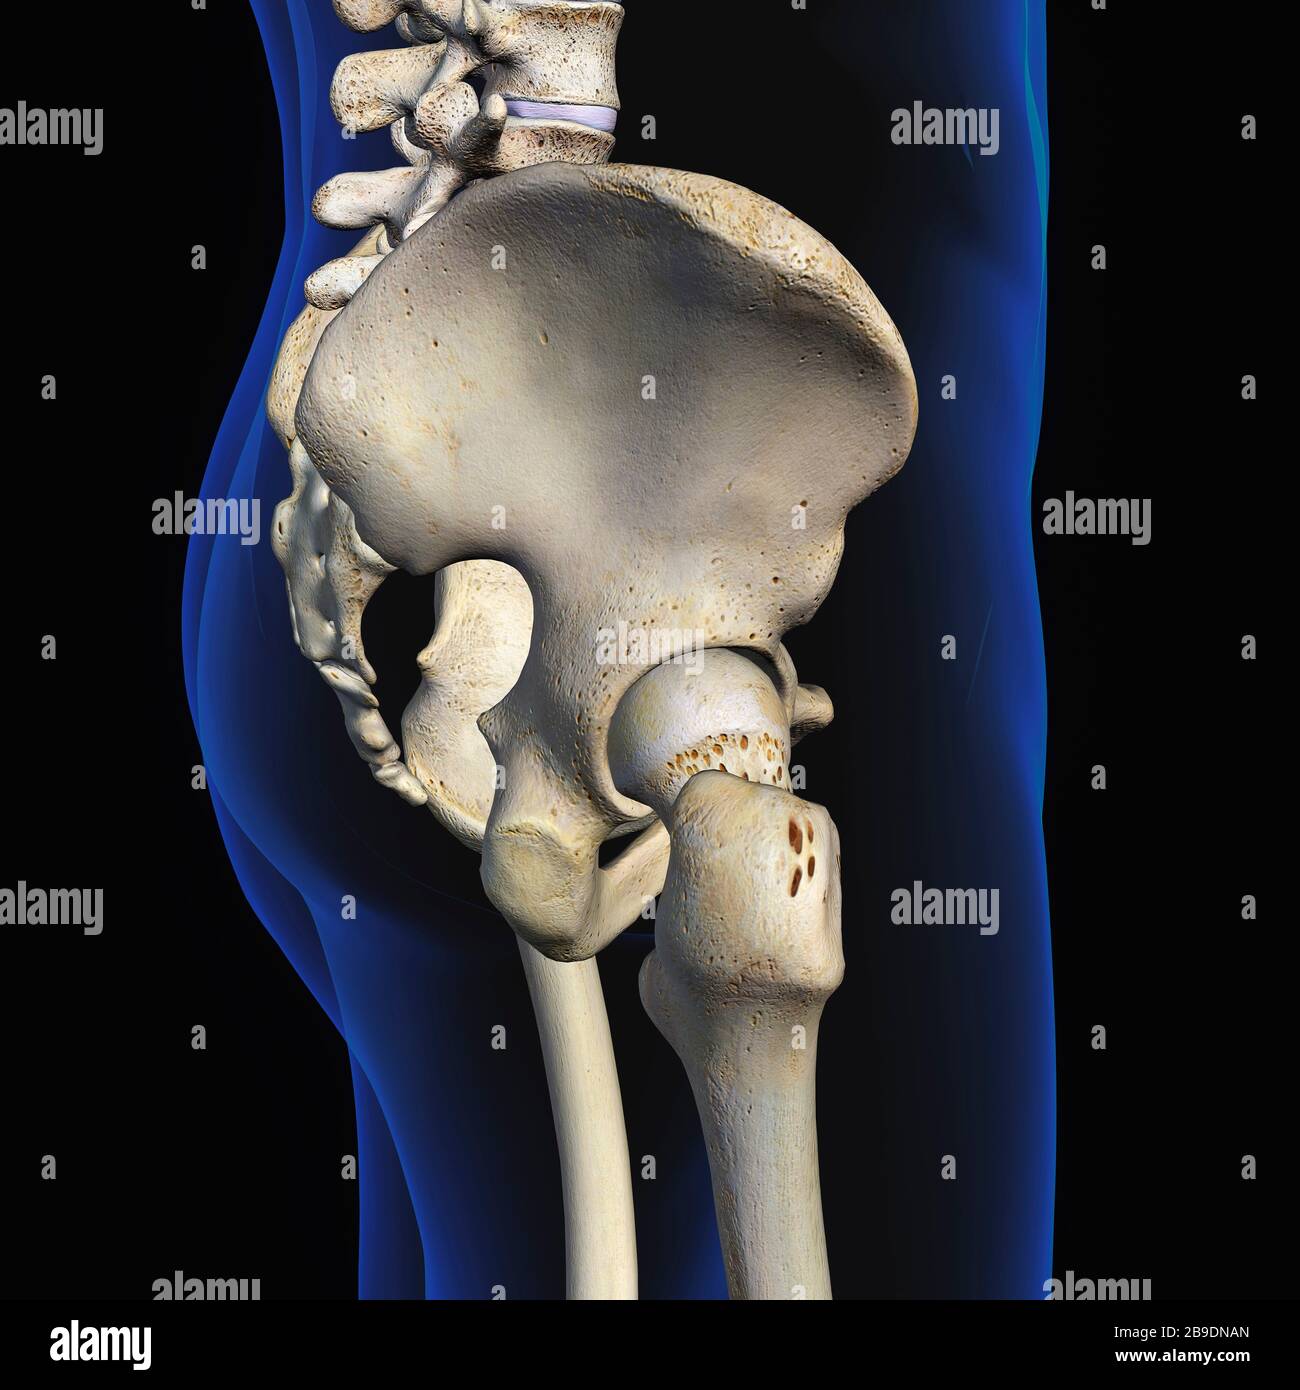

RFWW2CNW–Die männliche Anatomie, Gliedmaßen und hip Muskel- und Skeletterkrankungen Systeme, mit interner Muskelschichten. Vorder- und Rückansicht. schwarzen Hintergrund. 3d-Abbildung.